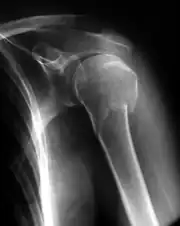

![]() Radiografía de una fractura conminuta del húmero izquierdo. | ||